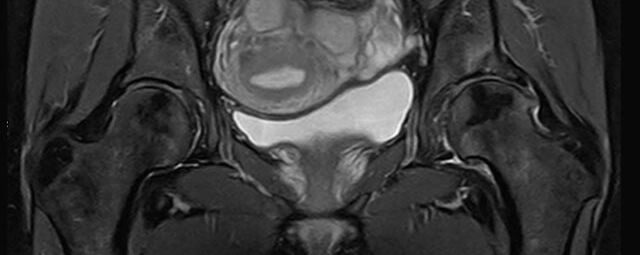

Abdomen/Becken

• Urogenitalorgane

• Tumordiagnostik z.B. im Bereich der Ovarien, des Uterus, der Prostata oder Harnblase

• dynamische MR-Analyse bei Beckenbodeninsuffizienz